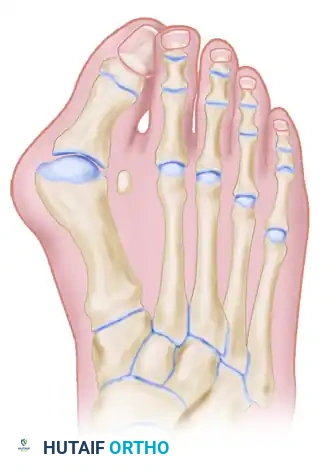

The classic "rheumatoid foot" presents with severe hallux valgus, dorsal subluxation or frank dislocation of the lesser metatarsophalangeal (MTP) joints, claw toes, hammer toes, and the formation of painful adventitial bursae. As the proximal phalanges subluxate dorsally, the plantar metatarsal fat pad is drawn distally, leaving the prominent metatarsal heads directly exposed to plantar pressure, leading to intractable plantar keratoses and ulceration.

Forefoot arthroplasty is directed primarily at the severe metatarsophalangeal joint deformities. The overarching goals are to relieve pain, correct deformity, improve cosmesis, enhance ambulatory function, and allow the patient to wear a reasonable variety of footwear.

ARTHRODESIS OF THE FIRST METATARSOPHALANGEAL JOINT

Biomechanical Positioning for Arthrodesis

The success of a first MTP fusion relies entirely on precise spatial positioning. Improper alignment will lead to gait dysfunction, interphalangeal joint arthritis, and transfer lesions.

* Valgus Alignment: Approximately 20 degrees of valgus.

* Dorsiflexion: 30 degrees of dorsiflexion in reference to the first metatarsal axis. (This equates to approximately 15 degrees of dorsiflexion in reference to the plantar aspect of the foot).

* Rotation: The hallux must be placed in absolute neutral rotation.

This specific alignment allows for a normal toe-off during the terminal stance phase of gait and accommodates a standard shoe heel height. Excellent gait patterns and improved first-second intermetatarsal angles are routinely achieved. Rarely is a proximal first metatarsal osteotomy necessary in conjunction with the arthrodesis.